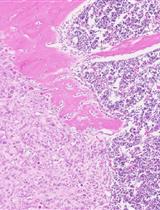

Gene rearrangements generate mixed-lineage leukemia (MLL) fusion genes, which cause highly aggressive acute leukemia. MLL-rearrangements are often associated with few additional genetic alterations and poor clinical outcomes (Andersson et al., 2015). Wild-type MLL enhances and maintains the expression of a subset of genes, including homeobox (Hox) genes, to stimulate the expansion of immature progenitors (Jude et al., 2007). The expression of Hoxa9 and Meis1 is highest in the immature progenitor/stem cell fraction, but gradually declines as cells differentiate, and eventually diminishes in terminally-differentiated cell fractions (Somervaille and Cleary, 2006; Yokoyama et al., 2013). The MLL fusion protein constitutively up-regulates the expression of target genes, including Hoxa9 and Meis1, to immortalize immature progenitor cells and cause leukemia in vivo (Ayton and Cleary, 2003; Lavau et al., 1997). To date, more than 130 different MLL-rearrangements have been identified (Meyer et al., 2017). Two-thirds of MLL-rearranged leukemia cases are caused by fusion with a gene that is part of the AF4 family-ENL family-P-TEFb (AEP) complex (Yokoyama et al., 2010). The MLL fusion proteins constitutively form an MLL/AEP hybrid complex on the target chromatin (Okuda et al., 2014; Yokoyama et al., 2010), which further associates with the SL1 complex to activate RNA polymerase II-dependent transcription (Okuda et al., 2015 and 2016). AEP-mediated transactivation of MLL target genes transformed myeloid progenitors ex vivo, but did not cause leukemia in vivo, which suggested that other function is additionally required for in vivo leukemogenesis (Okuda et al., 2017). Recently, we showed that the ability to recruit the DOT1L complex is necessary to cause leukemia in vivo in addition to the ability to recruit AEP using in vivo leukemogenesis model. Thus, the combinatorial use of the in vivo leukemogenesis model and myeloid progenitor transformation assay is necessary to dissect the functional properties of oncogenes. In this protocol, we describe the in vivo leukemogenesis model using retroviral transduction in detail.

Data analysis